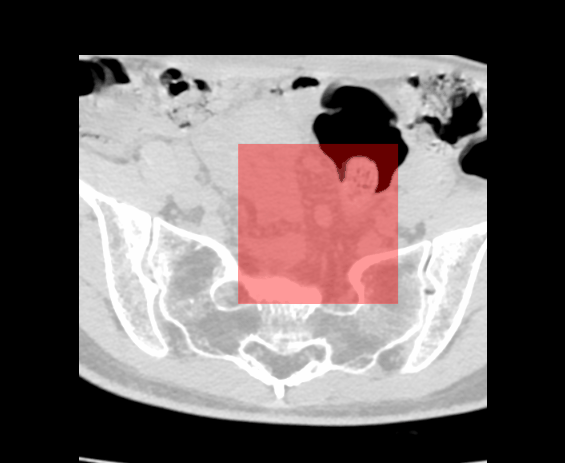

maskFilter->SetMaskedOutputValue(255, 0, 0);

maskFilter->SetMaskAlpha(0.4);

maskFilter->NotMaskOn(); // 255 不可见

3、勾画交互-矩形工具